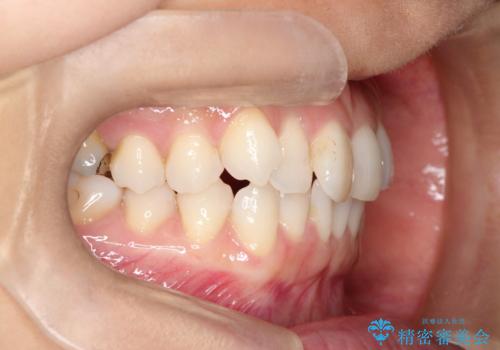

八重歯と前歯のガタガタをインビザラインで

- 八重歯と前歯のガタガタを主訴に来院されました。

目立たず矯正したいとのことでインビザラインで矯正することとしました。

インビザラインで目立たずに治療を終えることができ、喜んでいただけました。